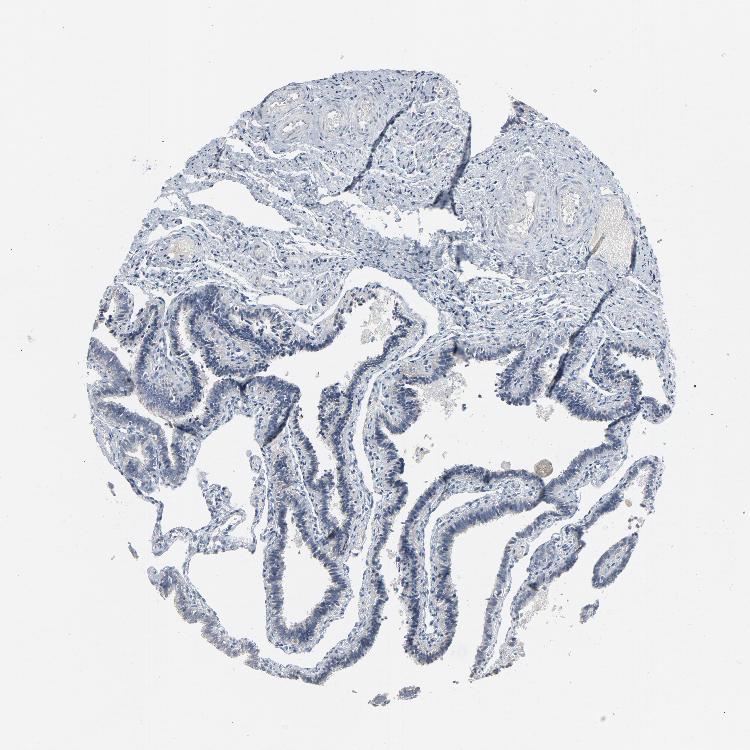

GPX2